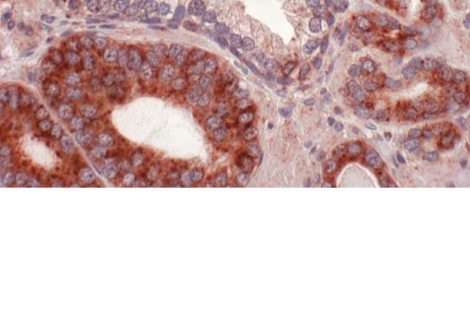

أراد علي وزملاؤه معرفة ما إذا كانت الخلايا الجذعية المتمايزة إلى مستقبلات ضوئية مخروطية يمكن أن تستعيد درجة معينة من الرؤية في الفئران ذات المخاريط غير النشطة. لقد طوروا نوعين مختلفين من المخاريط البشرية: أحدهما مشتق من الخلايا الجذعية الجنينية التي تعمل وتبدو طبيعية ، ونوع التحكم الذي ظهر طبيعيًا ولكنه لا يستجيب للضوء. تم اشتقاق مخاريط التحكم هذه من الدم المحيطي لشخص يبلغ من العمر 40 عامًا مصابًا بالعمى ، وهي حالة تؤدي إلى فقدان جزئي أو كامل للرؤية اللونية.

زرع فريق علي المخاريط في شبكية عين الفئران التي تمت تربيتها لتطوير مرض متقدم في العين ، مع وجود مخاريط غير وظيفية تمامًا. باستخدام هذه الفئران التي تم التحكم فيها لاحتمال أن الوظيفة المتبقية من المخاريط الموجودة ، بدلاً من المخاريط المزروعة حديثًا ، كانت مسؤولة عن أي تحسينات في الرؤية. للتأكد من أن الفئران لم تشن دفاعًا مناعيًا ضد الخلايا البشرية ، تم تربيتها أيضًا لتكون تعاني من نقص المناعة.

قام الباحثون بحقن المخاريط الوظيفية في شبكية عين 32 عين فأر ، والمخاريط الشاذة في 23 عينًا أخرى. في بعض الأحيان ، تلقت عين الفأر عمليات الزرع ، وأحيانًا واحدة فقط. كلا النوعين من المخاريط ، سواء كانا يعملان أم لا ، متصلان بشبكية العين لتكوين كتلة خلوية نموذجية للعين السليمة وضرورية للرؤية في الضوء الساطع.